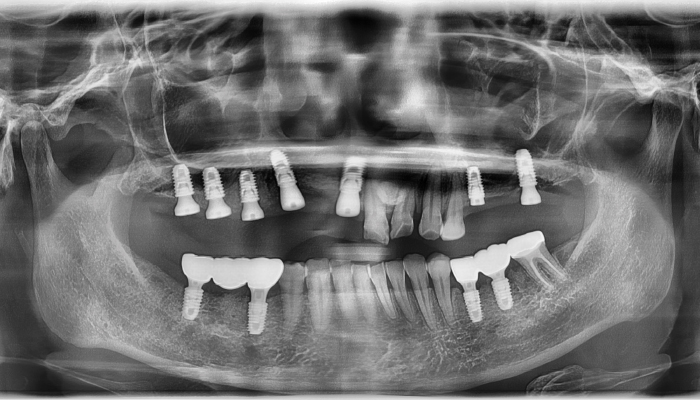

상악동거상술 수술사진

상악동거상술 전후 사례

• 식립 전

식립 후

• 식립전

식립후